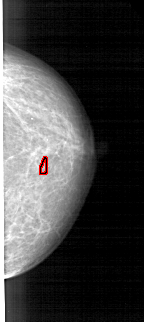

A_1489_1.LEFT_MLO

LEFT_MLO LINES 5491 PIXELS_PER_LINE 2266 BITS_PER_PIXEL 12 RESOLUTION 43.5 NON_OVERLAY

FILE: A_1489_1.RIGHT_MLO.OVERLAY

TOTAL_ABNORMALITIES 1

ABNORMALITY 1

LESION_TYPE CALCIFICATION TYPE PLEOMORPHIC DISTRIBUTION CLUSTERED

ASSESSMENT 4

SUBTLETY 2

PATHOLOGY MALIGNANT

TOTAL_OUTLINES 1

BOUNDARY